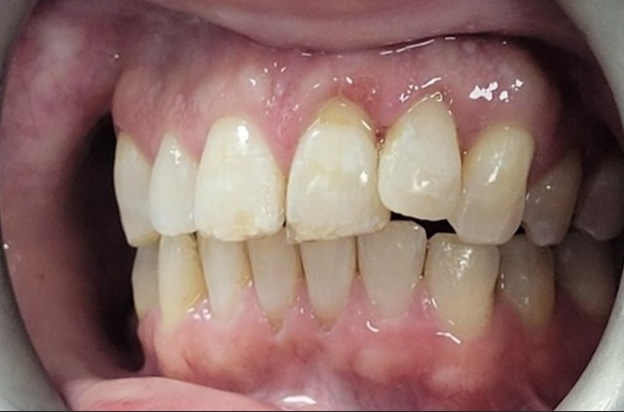

Dental trauma management

Pre-operative photo and X-ray

6 month review